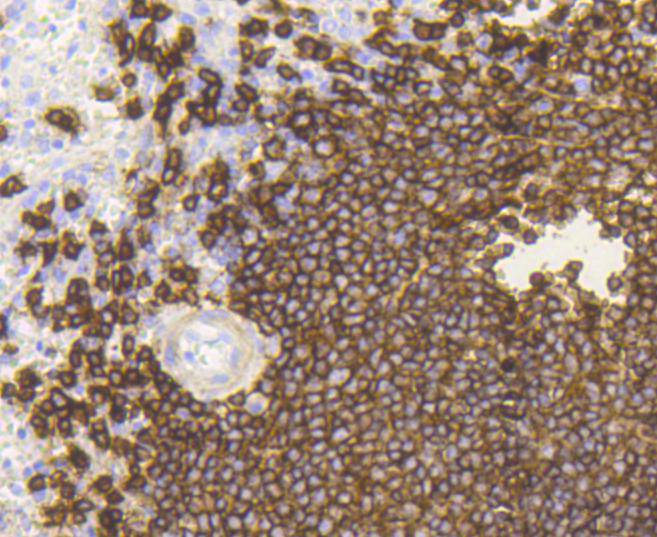

CD20 Rabbit mAb

WB, IHC, IP

WB: 1:1,000-5,000

IHC: 1:50-1:200